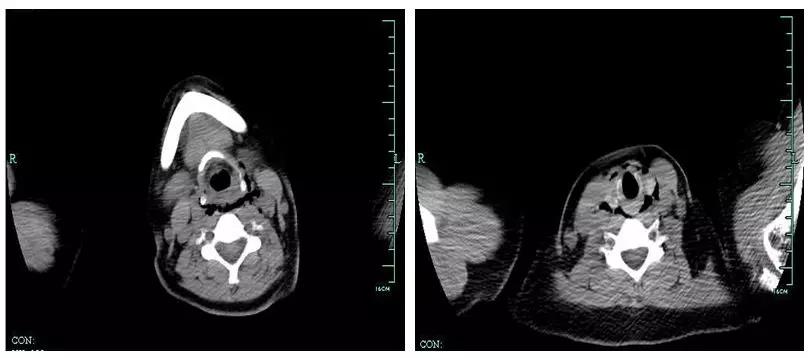

如图 1-3所示:

图 2:腹部 CT 显示胃小弯侧异物延续至胰腺颈体部